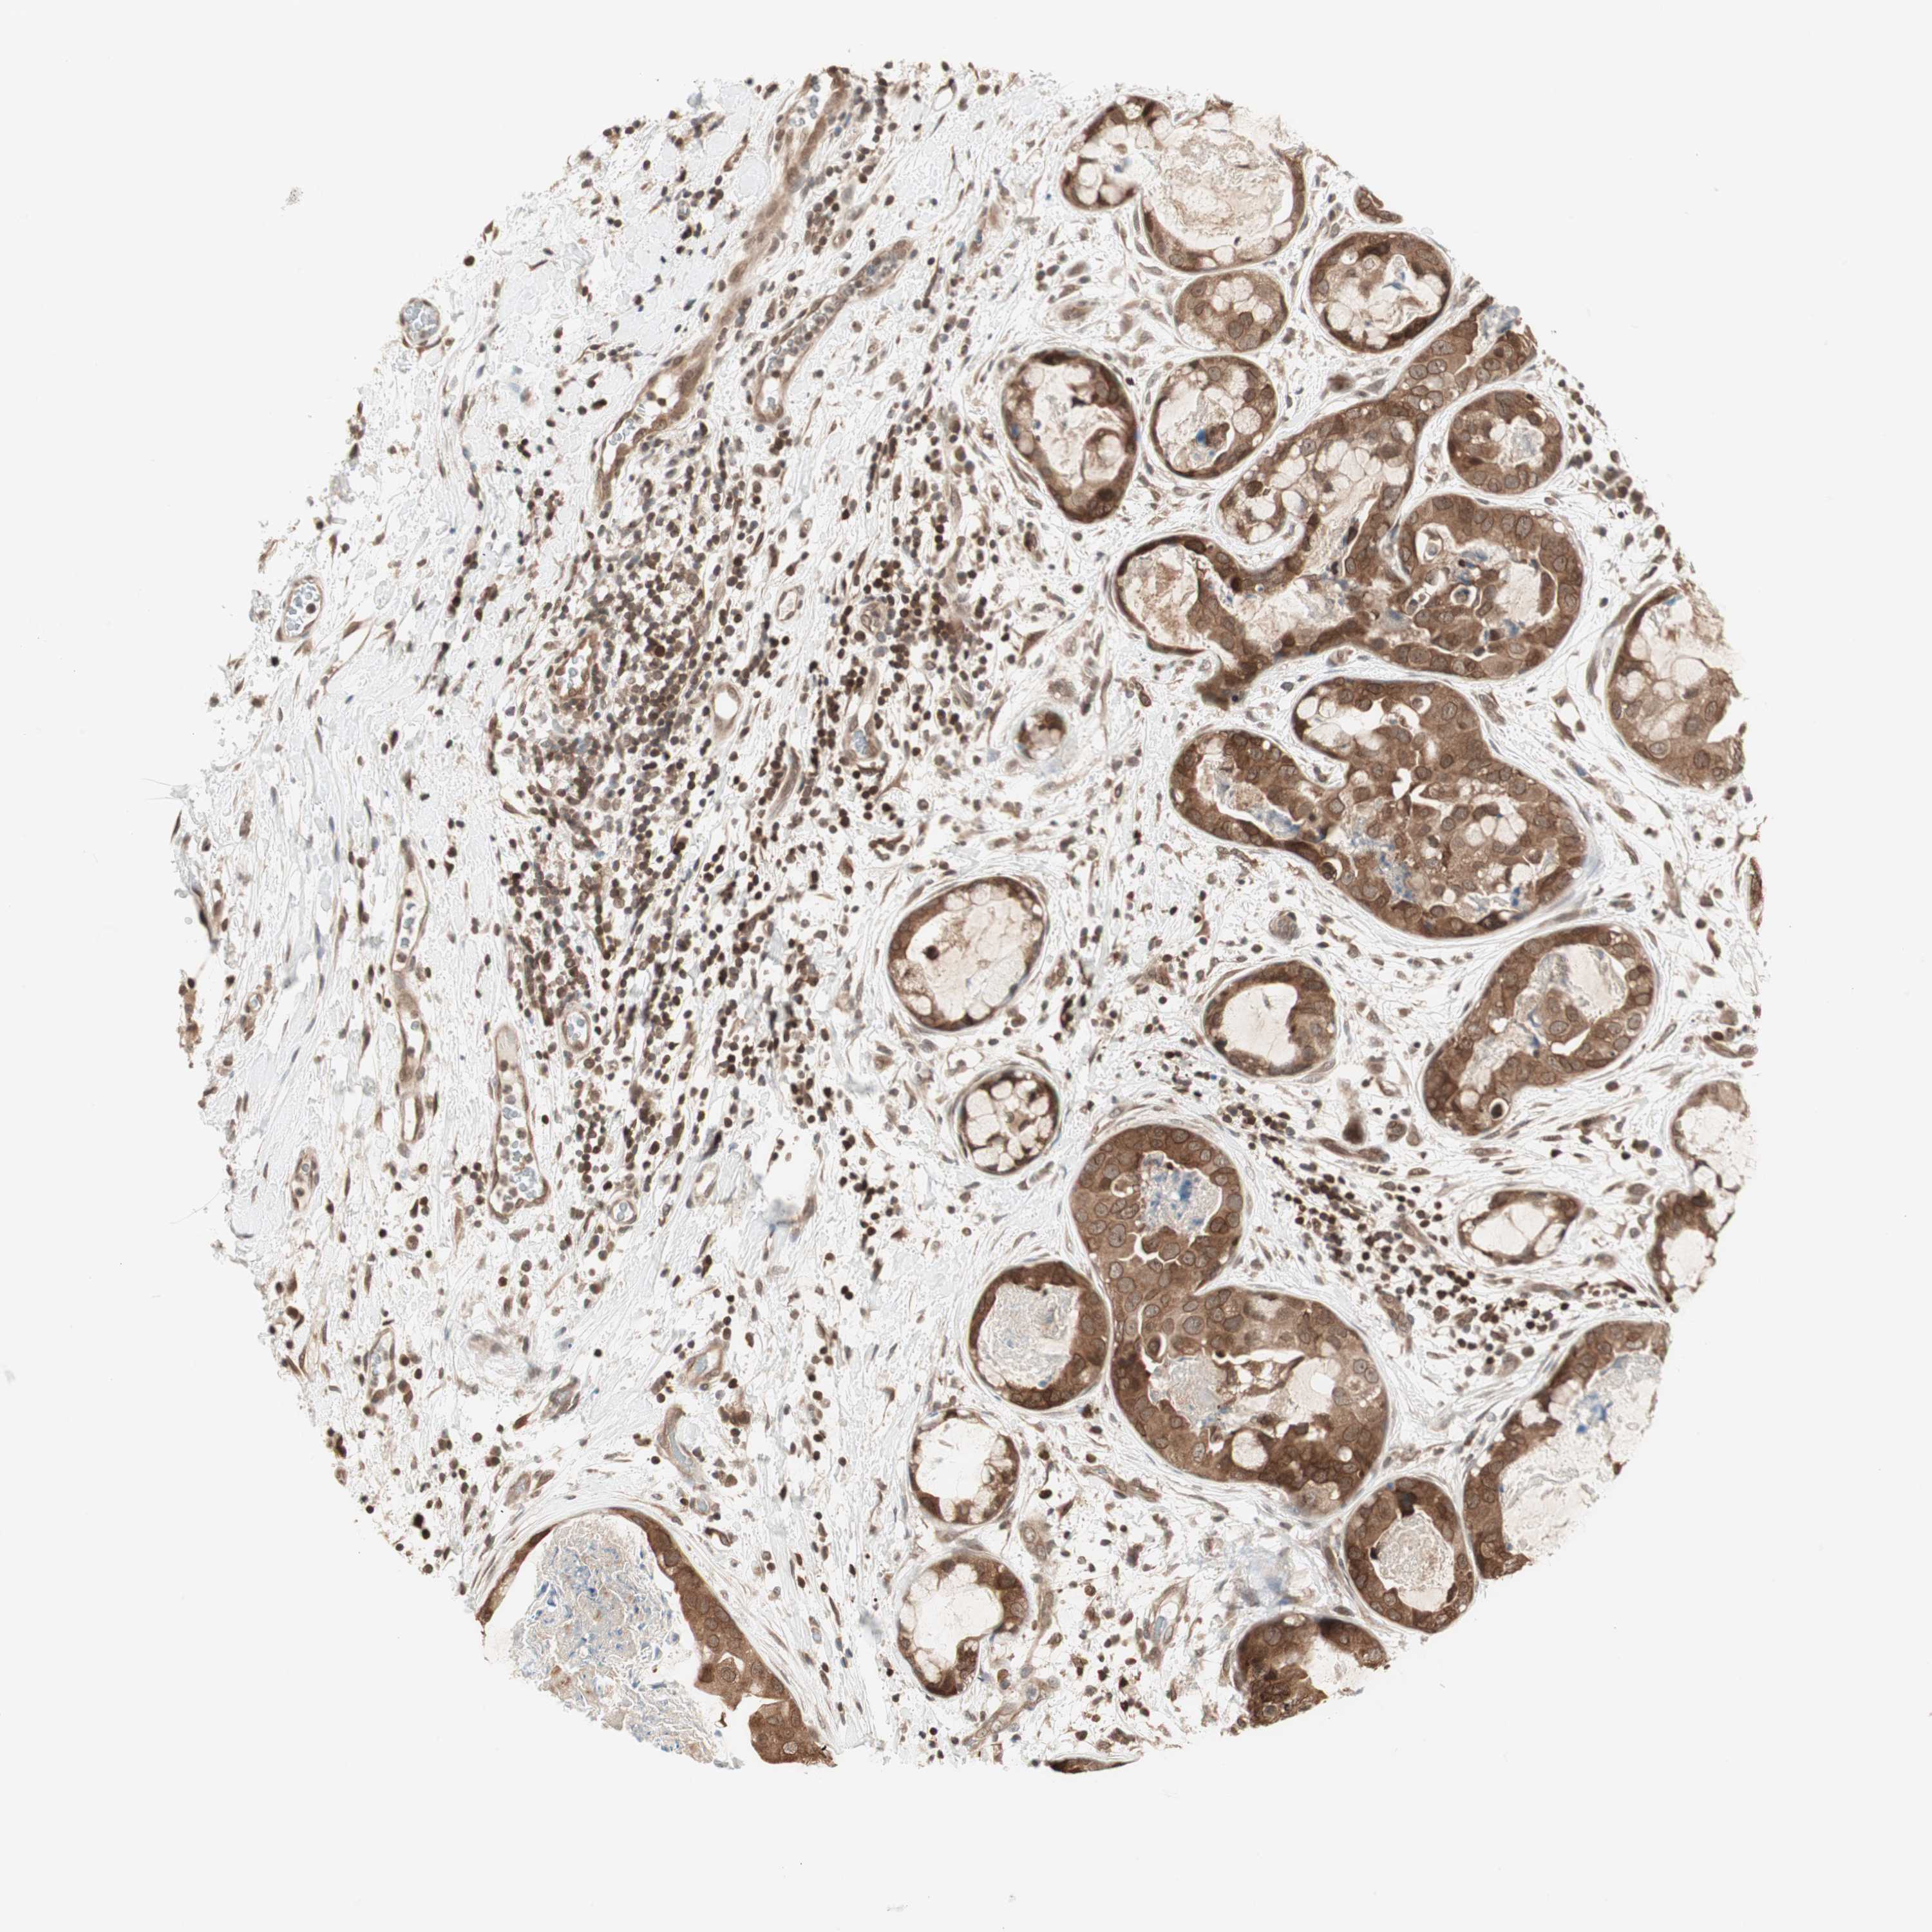

CANCER BREAST CANCER Show tissue menu

BRCA TCGA BRCA VALIDATION PROTEIN EXPRESSION